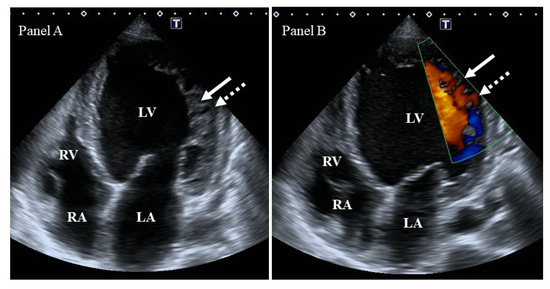

Background/Objectives: Heart failure (HF) causes systemic and regional haemodynamic alterations that extend beyond the heart, profoundly affecting splanchnic circulation. Venous congestion is a hallmark of heart failure (HF) and a major determinant of clinical deterioration and multiorgan dysfunction. The splanchnic venous system—comprising the portal, hepatic, and renal veins—acts as a key reservoir for intravascular volume redistribution. Conventional ultrasound (US), using grayscale and Doppler imaging, offers a direct, non-invasive approach to visualize these haemodynamic changes. This review, Part 1 of a two-part series, summarizes the current evidence and clinical applications of conventional US for assessing splanchnic, cardiac and pulmonary vascular alterations in patients with HF. Methods: A systematic review was performed in PubMed, Embase, and the Cochrane Library up to current date, following PRISMA 2020 guidelines. Eligible studies included adult human investigations evaluating splanchnic vascular changes in HF using B-mode, color Doppler, or pulsed Doppler ultrasonography. Exclusion criteria were pediatric, animal, or non-English studies and non-standard imaging methods. Data on ultrasonographic parameters, haemodynamic correlations, and prognostic value were extracted and qualitatively synthesized; Results: A total of 148 eligible studies (n ≈ 7000 patients) demonstrated consistent associations between HF severity and alterations in splanchnic, cardiac and pulmonary flow. Findings included increased bowel wall thickness, portal vein dilation with elevated pulsatility, and monophasic or reversed hepatic vein waveforms, all correlating with higher right atrial pressure and adverse clinical outcomes. The integration of these parameters into the Venous Excess Ultrasound (VExUS) framework enhanced detection of systemic venous congestion, in addition to the study of the cardiac and pulmonary circulation. Conclusions: Conventional ultrasound assessment of splanchnic vasculature provides valuable, reproducible insight into systemic congestion in HF. Incorporating hepatic and portal Doppler indices into standard evaluation protocols may improve risk stratification, optimize decongestion therapy, and guide management. Further prospective randomized and outcome-driven studies are required before VExUS-based therapeutic thresholds can be universally recommended and define prognostic thresholds. Full article

Figure 1